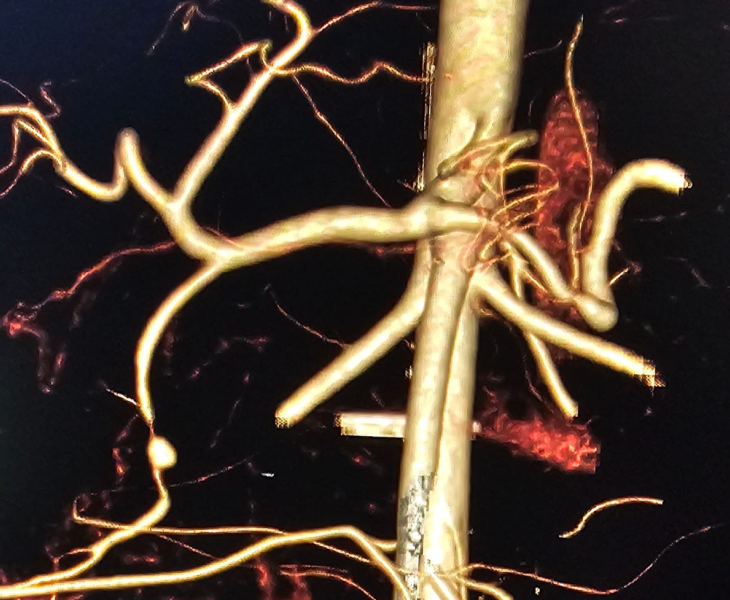

We use CT angiography and catheter angiography to identify the bleeding vessel precisely and then perform targeted embolization to seal it while preserving as much normal organ blood supply as possible.

Embolization is performed in a catheterisation lab under fluoroscopy (X‑ray) guidance, usually through a tiny puncture in the groin or wrist artery.

- Catheter angiography: contrast is injected to locate the pseudoaneurysm and bleeding source.